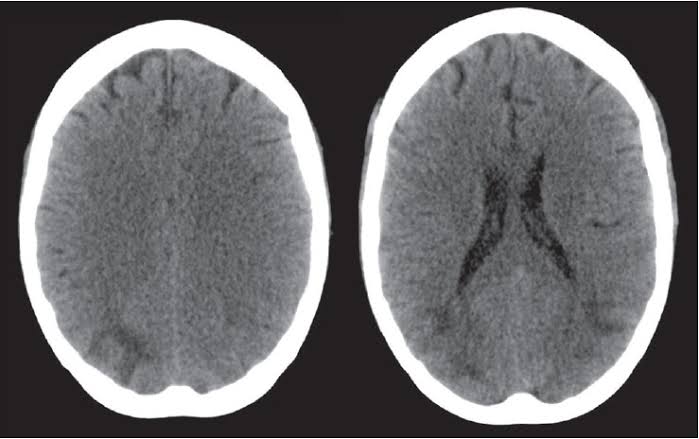

It is a very rare disease of central nervous system which affects the brain and spinal cord at the same time. When the recurrent bleeding happens into the subarachnoid space then it leads to the accumulation of hemosiderin deposits in the subpial layers of the brain and spinal cord.These hemosiderin deposits are basically the accumulations of the iron resulting from this blood. In some cases this disease is referred as superficial hemosiderosis in which the iron deposits from the blood seepage leads to the deposits in the neural tissues and this has association with the cerebrospinal fluid.

Due to these deposits some complications are being observed in the nervous system which are classified as neuronal loss, gliosis and demyelination of the neuron cells.

As this disease is very rare with a less understanding of the condition but the developments in MRI technique has made a lot of things clear and more understandable. The reasons behind the unintended bleeding are still unclear to some extent but the consequences can be stated clearly. When the blood accumulate in the arachnoid spaces and stays there for a longer time because of the lack of detection, then this prolonged contact of hemoglobin iron stimulates the brain’s microglial cell’s ability to biosynthesize “ferritin”. This ferritin production is considered to be harmless to brain until this excessive deposit shatter and cause damage to the neural tissues. The detailed progression behind this damage is the subsequent free radicals and lipid peroxidation caused by the over production of the ferritin by the microglial cells leading to the ultimate neural damage.